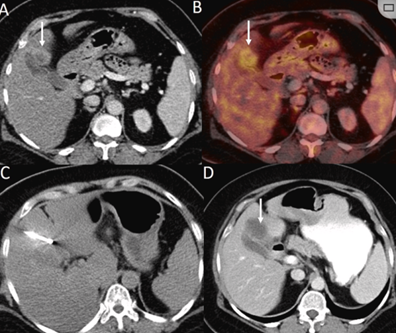

CT引导下冷冻消融

undefined

79 岁男性,肝转移(结直肠癌)肿瘤的完全消融病例

( a ) 轴向 MRI 和 ( b ) 轴向 CT 显示肝S8段有一个16mm的病灶,邻近肝缘。

( c )冷冻消融期间CT显示放置了2个冷冻探针,低密度冰球包围病灶。

(d)术后1个月随访 CT显示冰球对应的坏死区域,未见复发。

(e)术后6个月的CT,坏死区域缩小,未见复发。

(f)与基线影像(g)相比,12个月后的FDG-PET/CT显示未见FDG摄取。